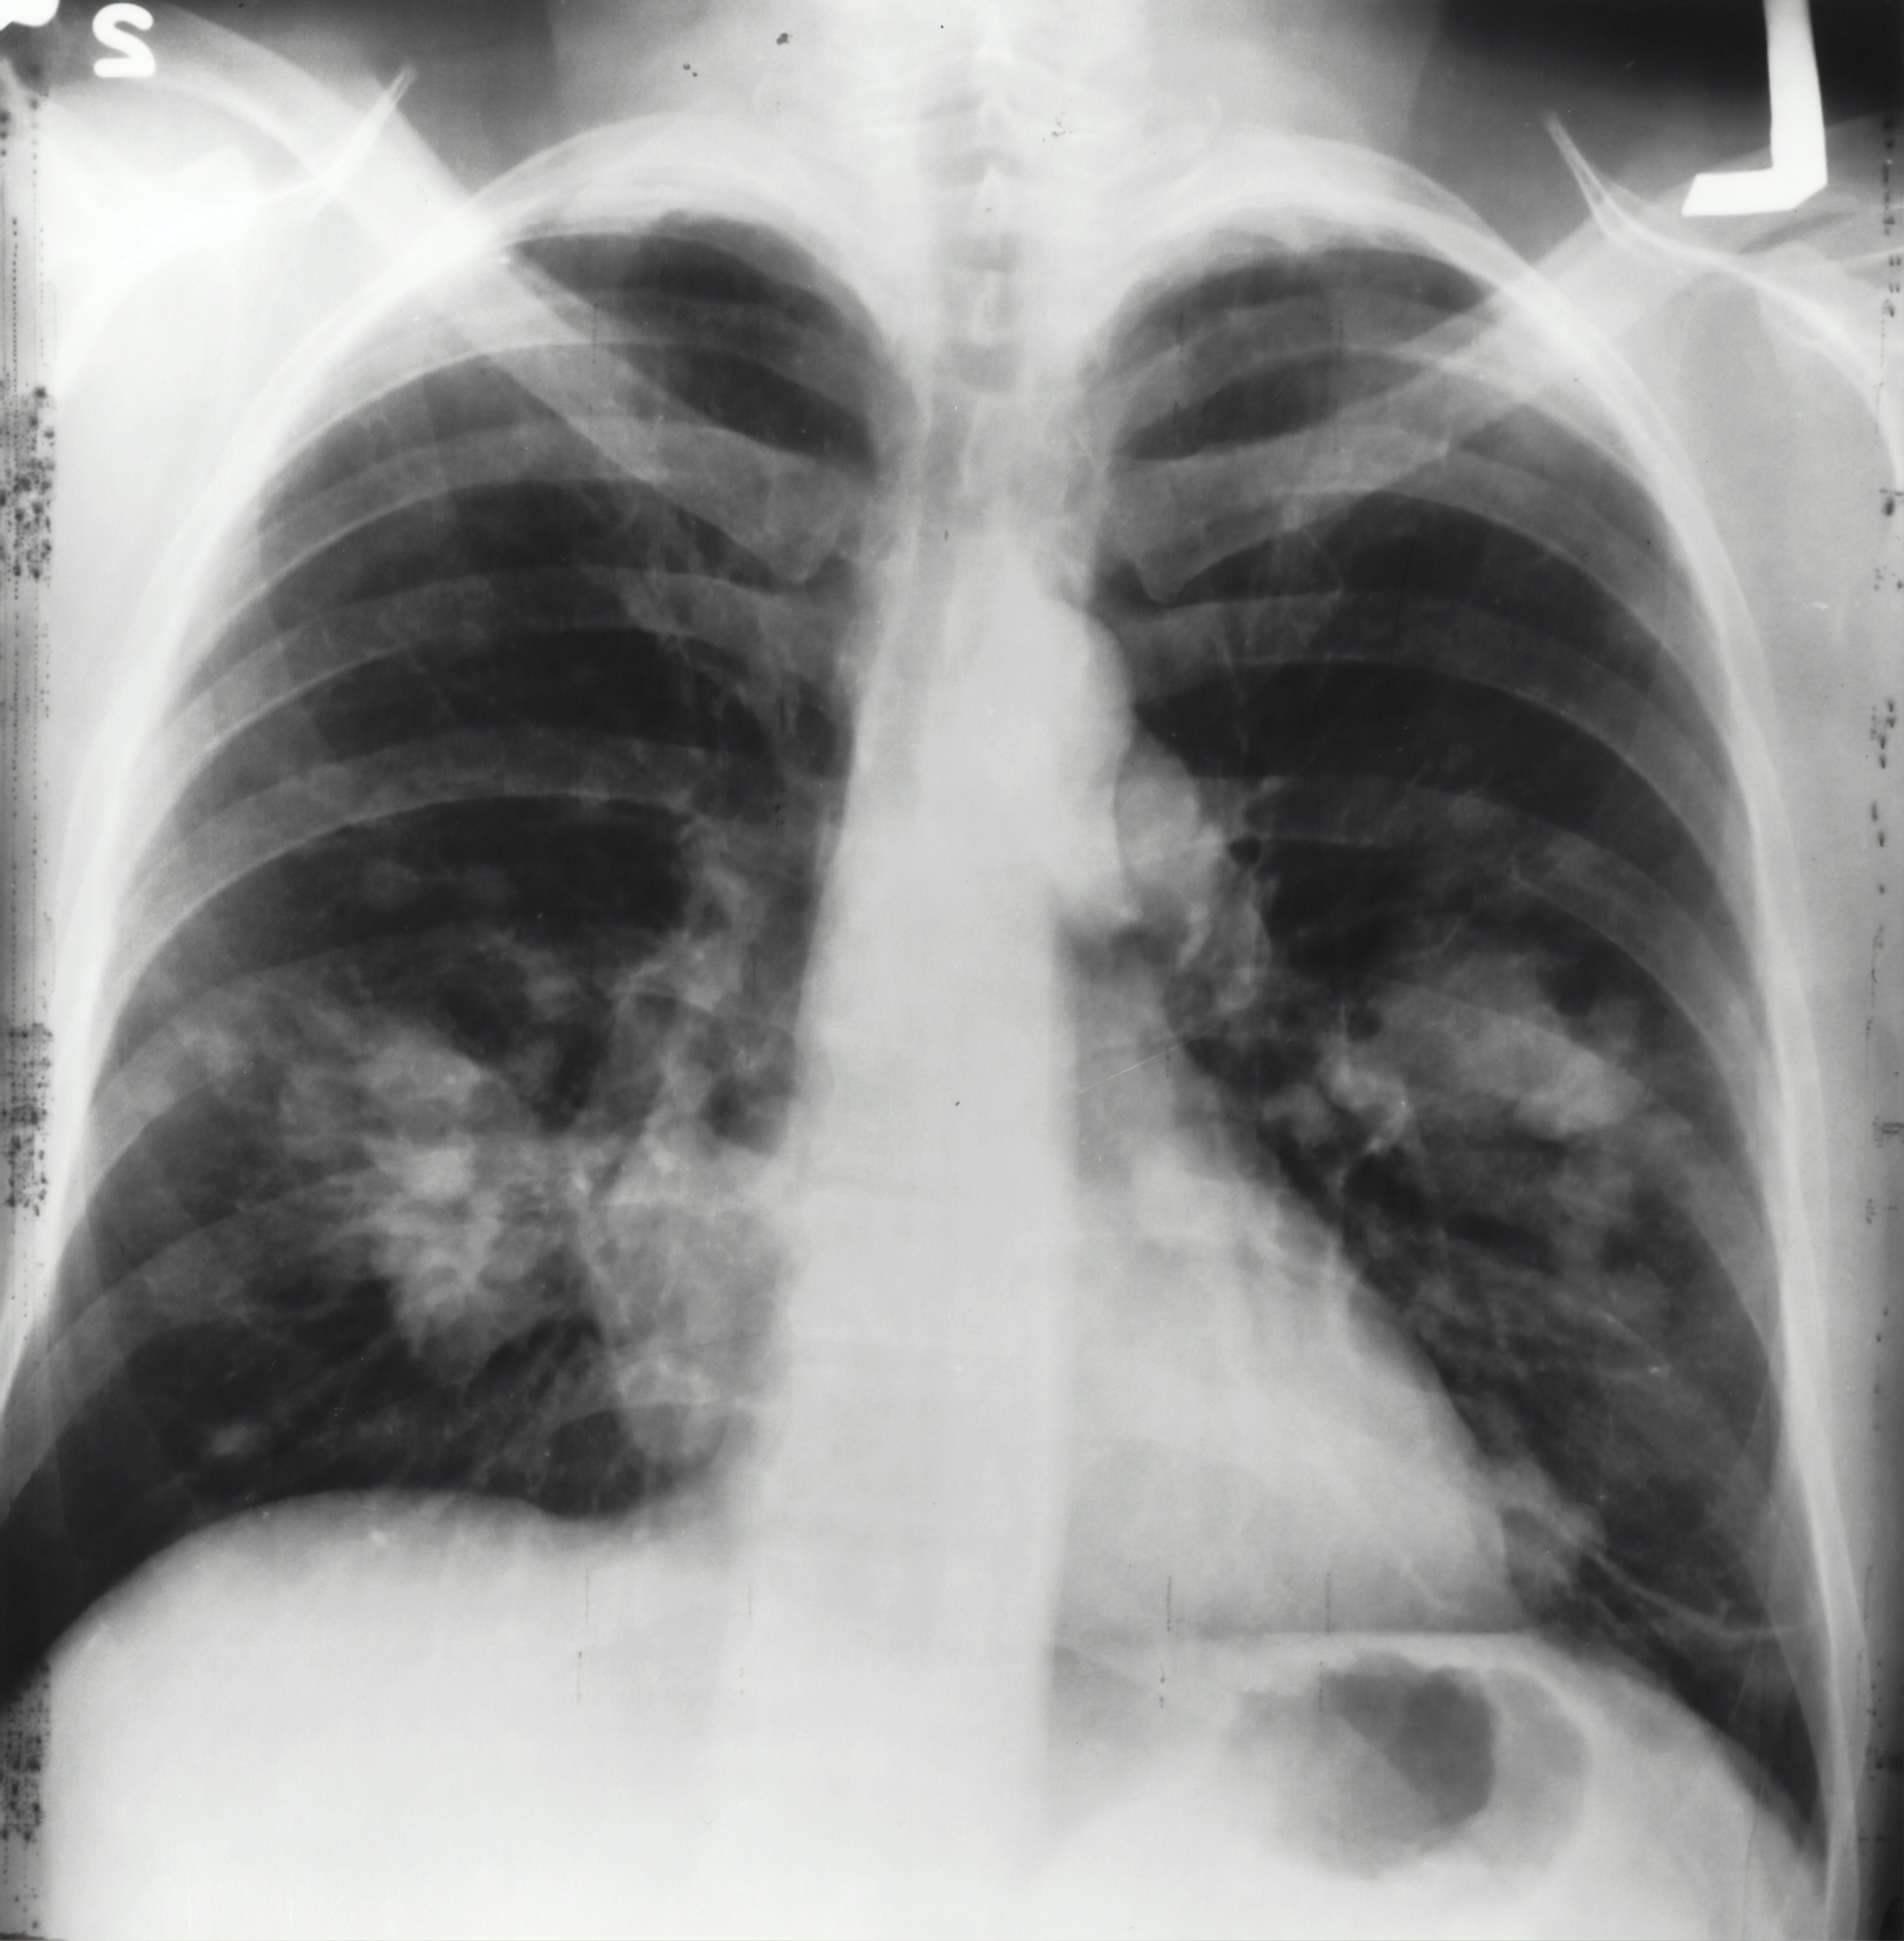

천식, 폐렴, 기흉, 기관지염 등 호흡기 질환도 가슴 답답함을 초래할 수 있습니다. 특히 천식이나 만성폐쇄성폐질환의 경우, 숨쉬기 어려운 느낌이 동반될 수 있습니다.

증상: 호흡곤란, 기침, 가슴 답답함이 나타날 수 있습니다.

관리: 기침이나 호흡에 문제가 있다면 즉시 병원에 방문하여 치료를 받는 것이 필요합니다. 흡연을 피하고, 공기가 오염된 환경에서 장시간 노출되지 않도록 합니다.